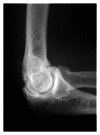

Primary and posttraumatic arthritis of the elbow

Whether degenerative joint disease of the elbow may be the result of primary or posttraumatic etiologies, arthritis of the elbow commonly leads to pain, loss of motion, and functional disability. A detailed history and focused physical examination, in combination with imaging modalities, can help localize the origin of symptoms and help direct treatment. Although nonoperative treatment is the initial therapy for arthritis of the elbow, surgical interventions may provide substantial relief to the appropriately selected patient.